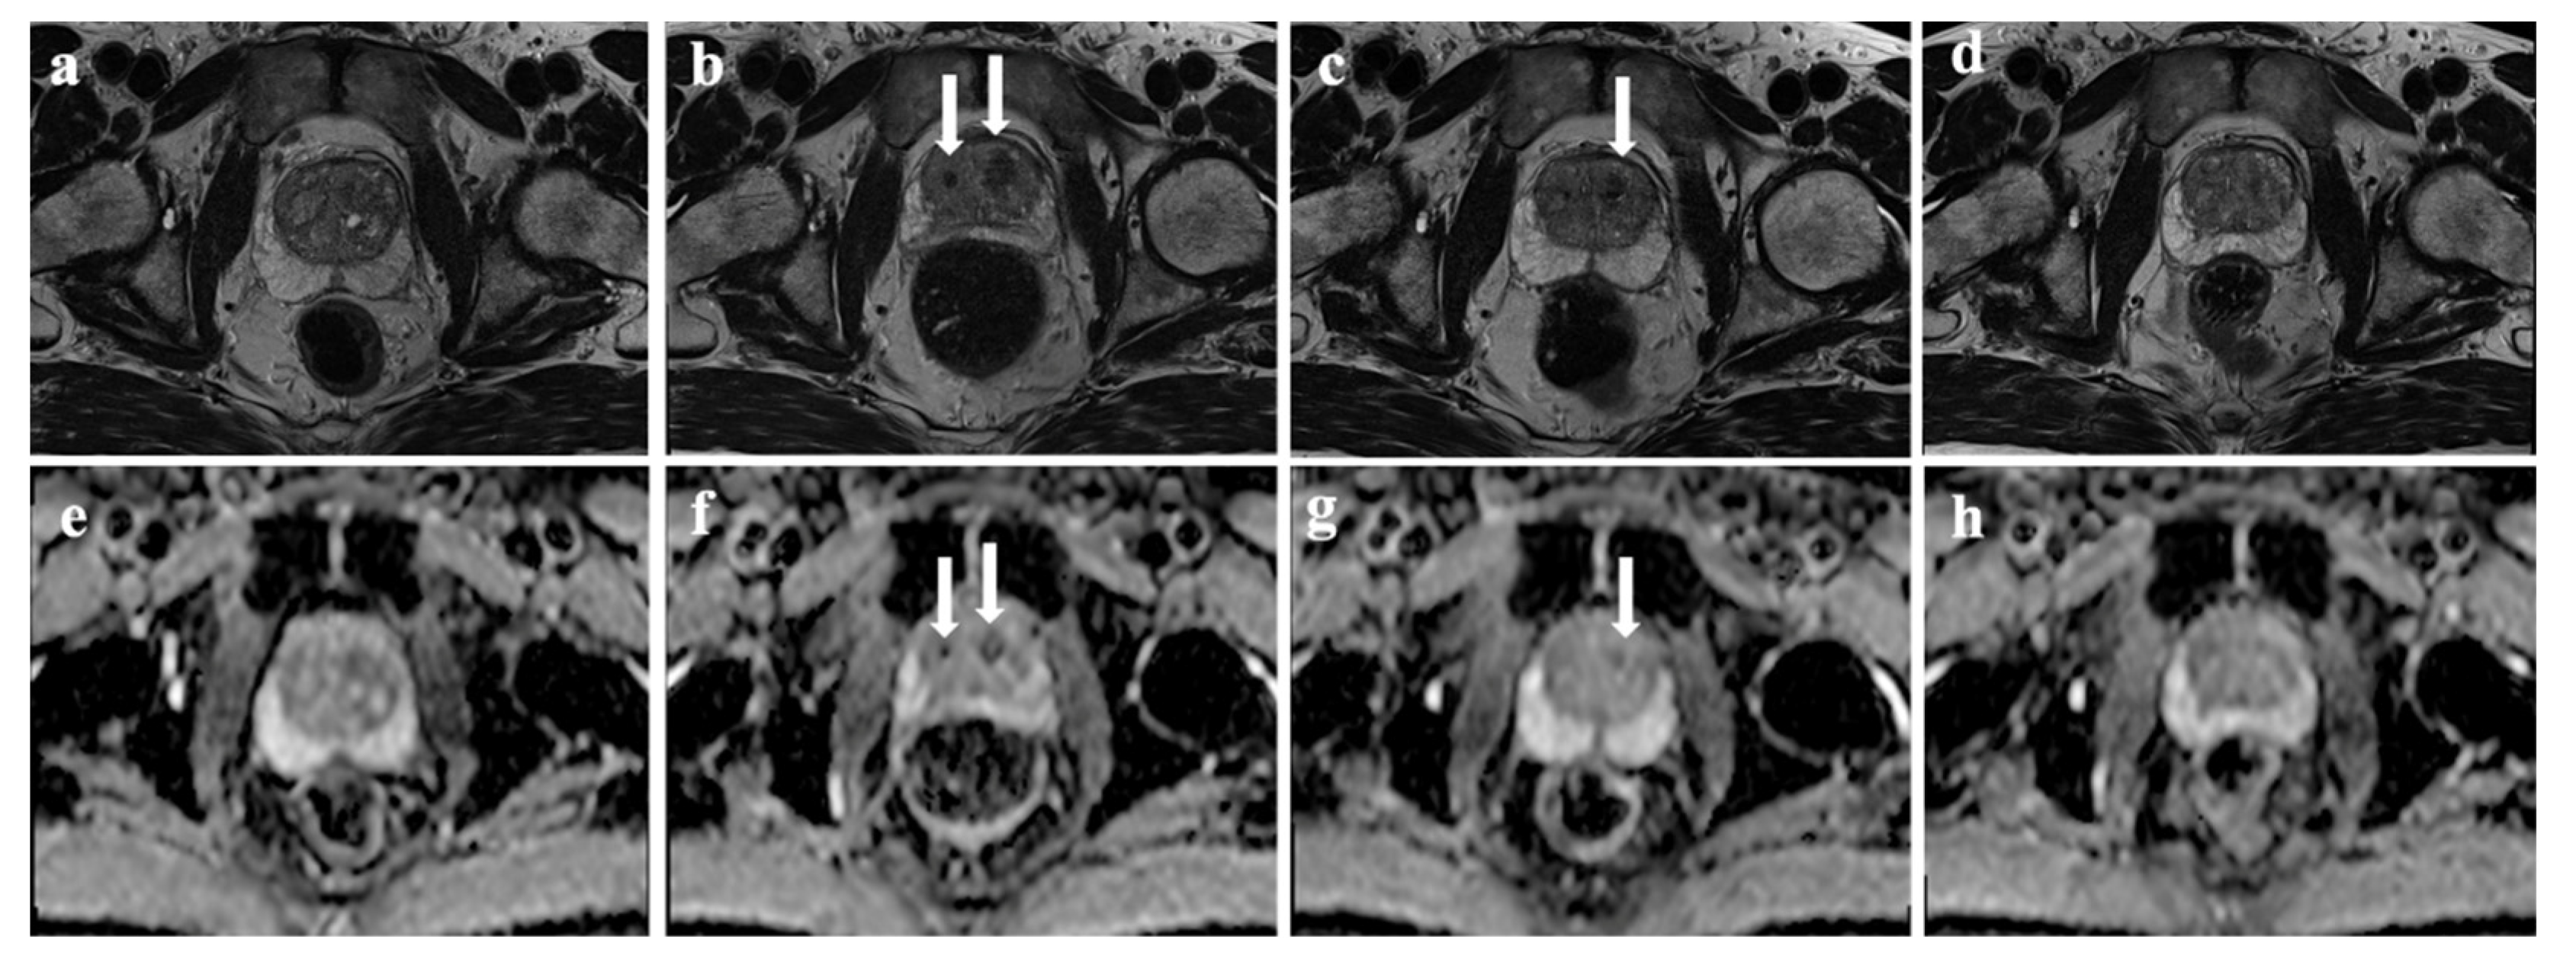

3.4. Clinical Indexes